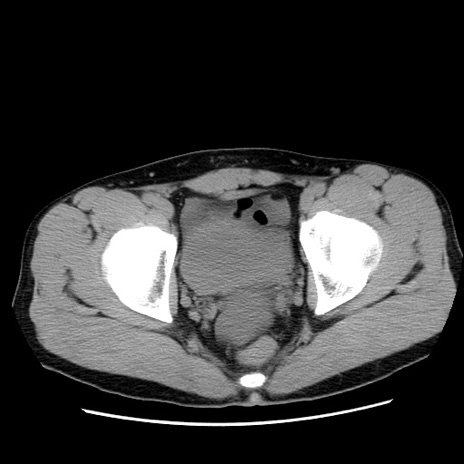

冠状断像

【症例】20歳代 男性

【主訴】心窩部痛

【現病歴】今朝より上腹部痛あり。一旦軽快していたが再度出現したため救急要請。昨日夕に白身の魚を含む刺身を食べた。

【身体所見】BP 136/89mmHg、HR 74/min、BT 37.0℃、腹部:膨満、軟、心窩部に圧痛あり。反跳痛なし、筋性防御なし、腸雑音やや亢進あり。

【データ】WBC 17700、CRP 0.48